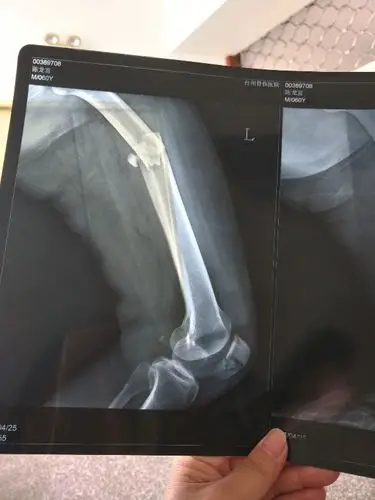

左侧股骨近端粉碎性骨折.患者,男75岁,因摔伤致左大腿疼痛伴 - 抖音

我爸大腿腿骨完全断了和膝盖粉碎性骨折 还有生殖器旁边的骨头有点裂

股骨远端开放性粉碎性骨折伴脱位 [病例帖]

粉碎性骨折!女子上瑜伽私教课,被教练压断大腿